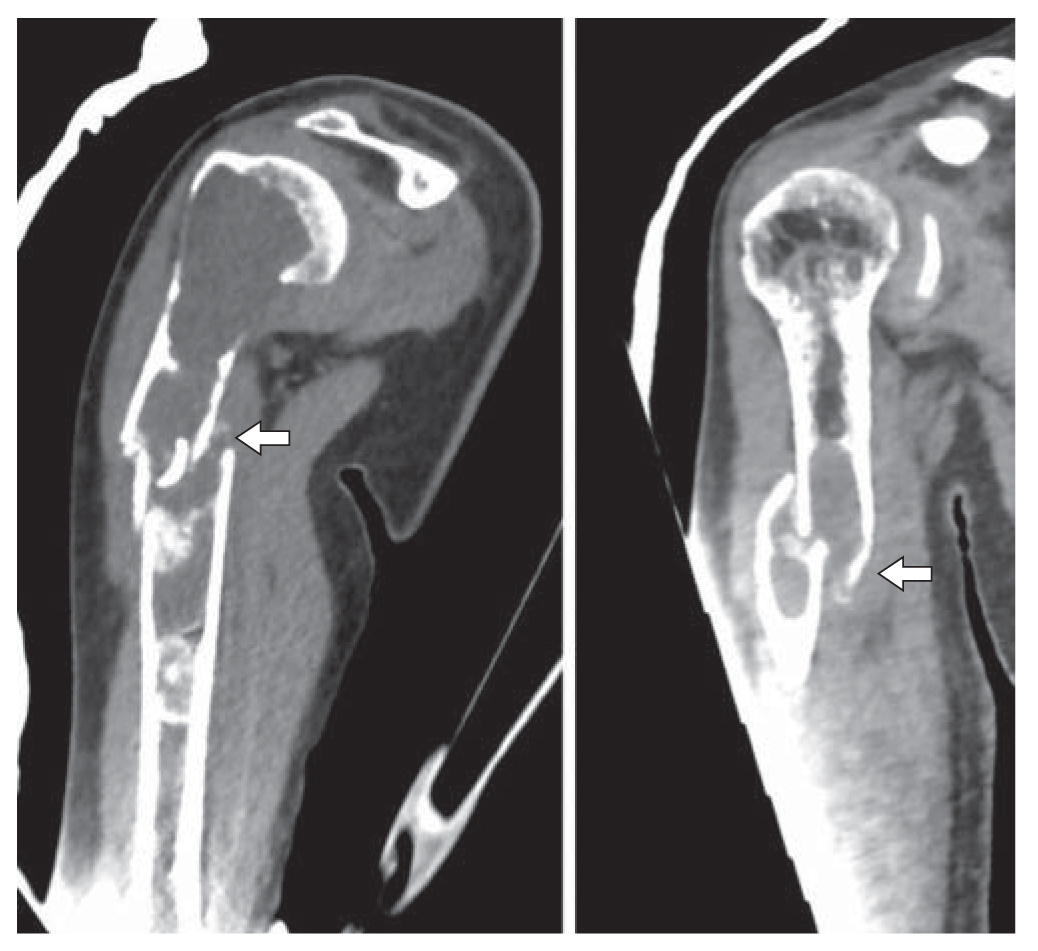

На третьи-четвертые сутки с момента операции отмечено появление субфебрильной лихорадки к вечеру с подъемом на пятые сутки до фебрильной. В общем анализе крови – увеличение СОЭ до 31 мм/ч без признаков лейкоцитоза. В общем анализе мочи – лейкоцитурия до 29 в п/зрения. Проведена МСКТ органов грудной полости, органов брюшной полости и забрюшинного пространства с выявлением КТ-картины псевдомембранозного (?) колита, мезентериальной количественной лимфаденопатии, гиповентиляции в нижних долях легких и незначительного количества жидкости в плевральных полостях. Визуализированы повторно множественные конкременты в чашечках почек (рис. 1) и конкремент в мочевом пузыре, множественные образования костей (бурые опухоли, рис. 2), с наличием патологических переломов левой и правой плечевых костей (рис. 3). Отмечены послеоперационные изменения – неоднородность мягких тканей шеи с наличием включений газа и жидкости слева. Проводилась антибактериальная и дезинтоксикационная терапия. В остальном – послеоперационный период без осложнений.

Рис. 1. Конкременты в почках.

Рис. 2. Бурые опухоли.

Рис. 3. Левая и правая плечевые кости.